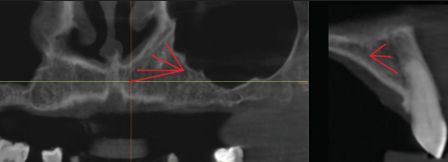

Некоторые авторы называют терминальную часть CS, расположенную в альвеолярном отростке верхней челюсти, по-разному: продолжение CS, добавочный канал CS или латеральный резцовый канал [рис. 1a и b]. Конечный участок канала может быть расположен в трёх направлениях: нёбном, центральном и щёчном.

Рисунок 1: Различные проекции КС (красные стрелки показывают топографию КС): A. Панорамный вид КЛКТ, КС визуализируется в боковой стенке носовой полости, проходя через альвеолярный отросток верхней челюсти. B. Поперечный вид КЛКТ, часть КС расположена с небной стороны в альвеолярном отростке верхней челюсти.